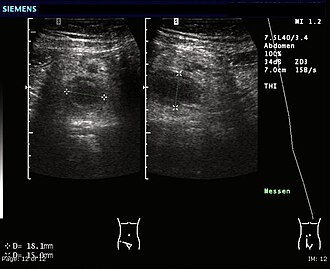

Ultrazvuk (UZ) abdomena (trbuha)

UZ abdomena može prikazati proširenje crvuljka i nakupljanje slobodne tekućine u trbušnoj šupljini, ali u slučaju kada crijeva sadrže puno zraka, crvuljak se ne mora prikazati.